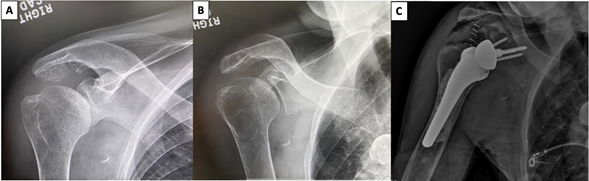

The patient underwent a reverse total shoulder arthroplasty (RTSA) based on his rotator cuff pathology and debilitating symptoms in 2020. A preoperative radiograph of the shoulder is portrayed in Figure 1A and B with appreciation of pathologic subacromial changes with the ultimate treatment of a RTSA depicted in Figure 1C. Intraoperative inspection revealed a large soft tissue mass, measuring 6.5 x 3.2 x 2.0 centimeters, in the area of the supraspinatus footprint (Figure 2A-2D). Additionally, abnormal appearances of the humeral head (Figure 3), soft tissues, glenoid rim, and labrum were observed. Histological specimens of intra-articular soft tissue, labrum, and synovium were obtained and confirmed the diagnosis of amyloidosis (apple-green birefringence by Congo Red Staining) and showed focal calcium pyrophosphate deposition (Figure 4A & 4B). Additionally, histology specimens of the undecalcified bone tissue showed moderate secondary hyper-parathyroid bone disease with peri-trabecular amyloid deposits (Figure 5A-5F).

Figure 1 (A) Preoperative anteroposterior, (B) preoperative Grashey, and (C) postoperative anteroposterior radiographs.